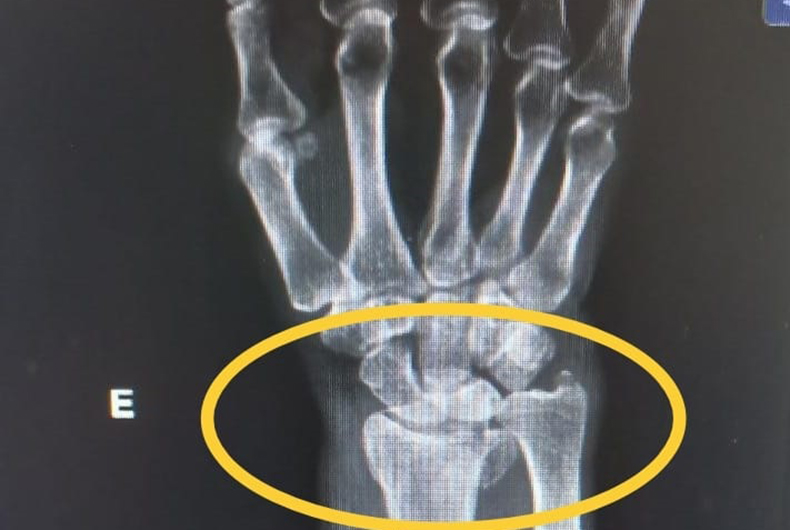

Na tarde desta quinta-feira, 5, policiais civis de Sobradinho prenderam preventivamente um homem de 41 anos após ele ter quebrado o braço da própria mãe, de 66 anos. Conforme a delegada Graciela Foresti Chagas, que coordenou as investigações e representou pela prisão, o suspeito possui antecedentes por roubo e furto.

Ele derrubou a vítima no chão, arremessou uma cadeira, tentou arremessar a mesa da cozinha e, por fim, tentou lhe desferir golpes de faca. A vítima foi socorrida por dois netos, quando conseguiu se arrastar para fora da residência. Mãe e filho residem na localidade de Santa Marta, no interior do município de Ibarama.

Após procedimentos legais, o suspeito foi recolhido ao Presídio Estadual de Sobradinho. A mulher será submetida a intervenção cirúrgica. Essa já é a segunda prisão na semana por violência doméstica praticada por filho contra mãe.